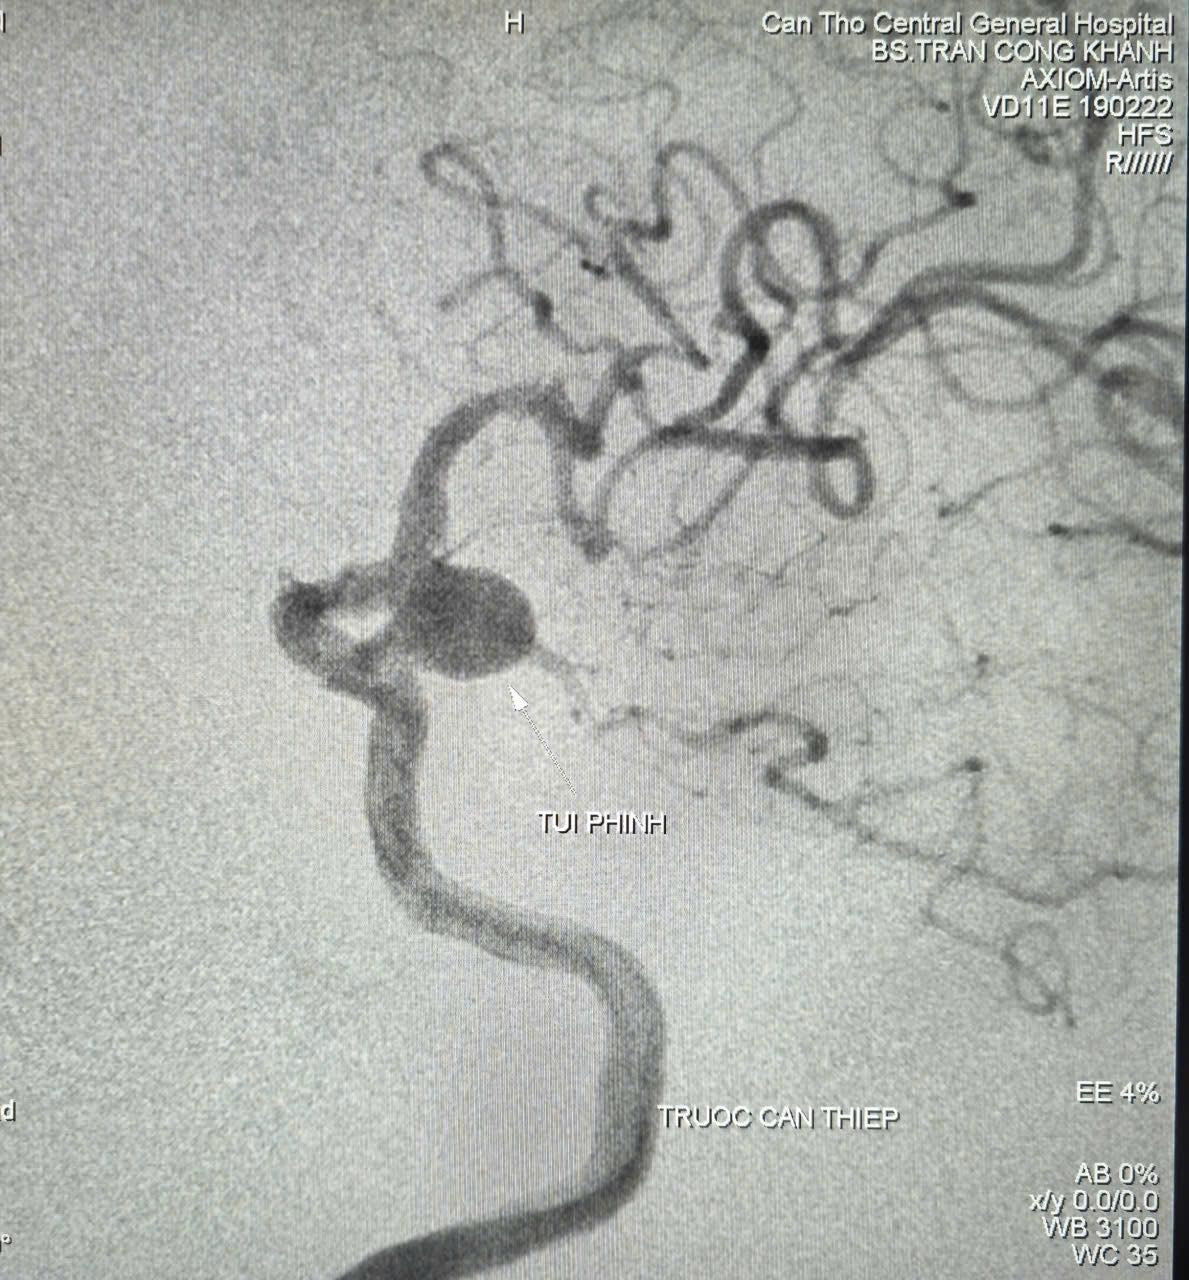

Hình ảnh túi phình trên phim chụp - Ảnh BVCC

Kết quả chụp cắt lớp vi tính và cộng hưởng từ cho thấy nhiều tổn thương cũ vùng não, túi phình đoạn gốc động mạch cảnh trong - thông sau bên trái, kích thước 9,2mm x 12mm, túi phình đang phát triển qua thời gian theo dõi (nguy cơ vỡ trong 5 năm khoảng 17.8%, ước lượng theo thang điểm PHASE 12 điểm ).